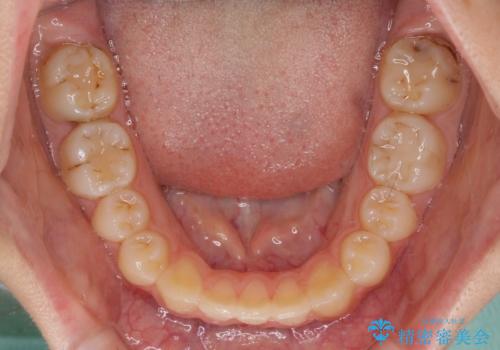

まずは補助装置を用いて八重歯を改善し、インビザラインにて歯列を整えましたが、当初の懸念が的中し、臼歯部の咬合を安定させることができませんでした。

海外留学の予定もあったため、後半は上下ワイヤー装置にて矯正治療を継続し、違和感なく咬合させることとなりました。